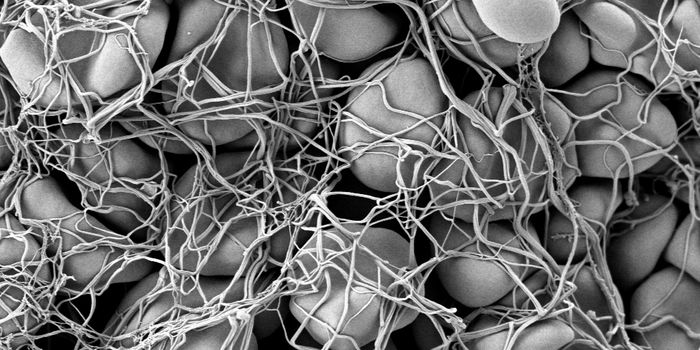

MAY 02, 2024CancerWe interact with small, single-cell organisms on a regular basis. These tiny cells, known as bacteria, represent a ...